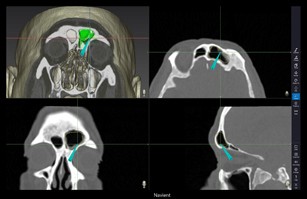

Navigate in 3D & 2D views, Smart 3D front clip, display 3D sinus model

• Smart 3D automatic front clip

• Smart Zoom magnifies navigation area

• Instrument tip accuracy verification